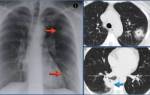

Для визуализации патологического процесса назначается рентгенологическое исследование органов грудной клетки, которое позволяет обнаружить изменения в легких. Обнаруживаются изменения с обеих сторон, преимущественно в нижних отделах легких.

Отмечаются усиление и деформация легочного рисунка, постепенно формируется картина так называемого «сотового легкого», которое характеризуется образованием кольцевых теней диаметром 3 – 7 мм со стенками толщиной до 3 мм, что в некоторой мере напоминает пчелиные соты.

Более детальную оценку структурного состояния легких дают компьютерная томография (КТ) и магнитно-резонансная томография (МРТ). В тяжелых случаях, когда вышеперечисленные методы исследования не позволяют выставить правильный диагноз, прибегают к помощи биопсии легкого, которая позволяет подтвердить наличие рубцовой ткани на микроскопическом уровне.

- Рентген. По флюорограмме, где равномерно видно затемненные области верхнего участка или нижней доли легочной ткани, доктор может предположить фиброз. Чтобы убедиться, что это такое заболевание в действительности, необходимо продолжить исследование.

- Для подтверждения наличия фиброзных образований после рентгенографии назначается КТ и МРТ легких.